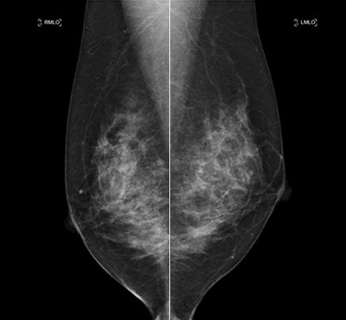

乳腺撮影

エックス線を用いた乳房撮影をマンモグラフィといいます。乳房の大部分は、乳腺を脂肪組織で構成されており、普通のエックス線検査で使用される装置では診断に有用な画像を得ることができません。マンモグラフィによって、視触診では分からない早期乳がんの発見が可能となります。

乳房は丸みを帯びているため、プラスチック板とフィルム支持台で乳房を挟み、均等な厚みにすることで乳腺の重なりを減らし、病変部の描出能を向上させ、少ないエックス線量で撮影することが可能となります。原則として2方向で撮影します。また撮影乳房は、症状がある側(検測)だけでなく、症状がない対側乳房も撮影します。通常のレントゲン撮影と異なり、軟エックス線を用いて撮影するため、髪の毛や薄い衣服なども障害陰影となるため、当院では基本的に上半身は裸の状態で撮影します。撮影時に髪が写り込む可能性がある時は髪をまとめていただくことがあります。また清涼パウダーボディー用ファンデーションなどはマンモグラフィでは障害陰影となる場合がありますので、ご使用をお控えください。検査において乳房の厚みを均一にして固定するため、痛みを伴う場合があり、全く痛みを感じない方、強く痛みを感じる方、人それぞれです。

乳房をそのままの厚みで撮影した場合、乳腺・血管・脂肪などの重なりで、病気があったとしても写真には写りません。乳房の病気には、0.1mm程度のとても小さな病変だけが早期発見の手掛かりになることもあり、そのため乳腺を広げて固定して、できるだけ乳房を薄く広げて撮影しなければ良い写真を撮ることはできません。我慢できるぎりぎりまで乳房を圧迫することは大変重要なことです。(圧迫板は一定以上の圧力がかからないよう設計してあります)ご協力お願いします。

基本の2つの撮影方向

• 内外斜位方向撮影(MLO)

• 頭尾方向撮影(CC)

その他、精密検査での拡大撮影や乳管造影検査などがあります。